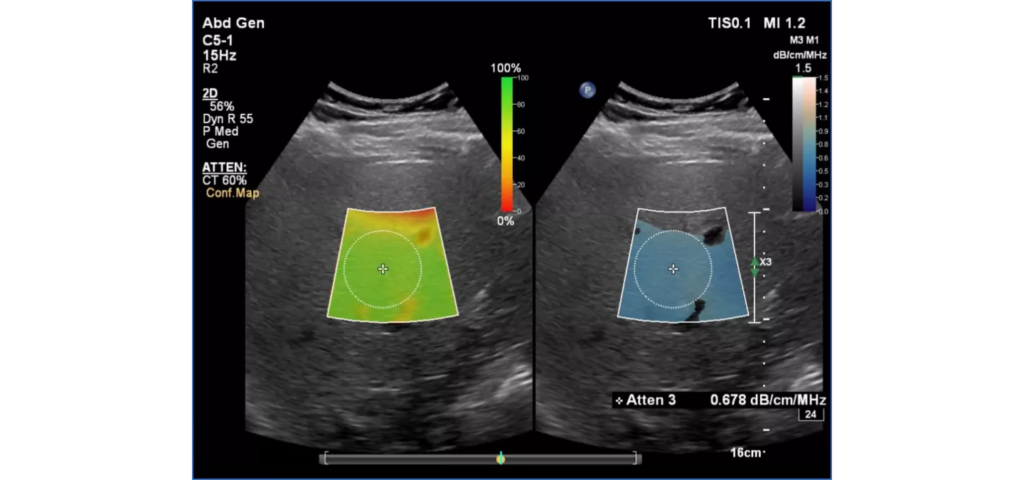

Philips EPIQ Elite ultrasound features an exceptional level of clinical performance, workflow, and advanced intelligence to meet the challenges of today’s most demanding practices. The EPIQ Elite platform brings ultimate solutions to ultrasound, with clinically tailored tools designed to elevate diagnostic confidence to new levels.